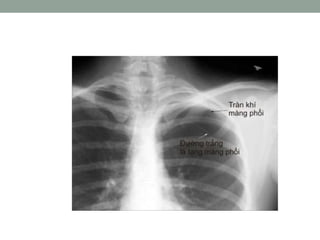

TRÀN KHÍ MÀNG PHỔI

XQUANG

• Tăng sáng bên có TKMP.

• Khoảng liên sườn giãn

• Phổi bị co lại thành một cục xẹp xuống sát rốn phổi.

• Cơ hoành không di động và bị đẩy xuống,

• Trung thất bị đẩy sang bên lành